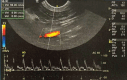

Ultrasound (USG) is a valuable diagnostic tool for evaluating the gastrointestinal tract of cats, providing noninvasive and dynamic information. B-mode USG allows evaluation of intestinal wall thickness, stratification, motility, and adjacent structures, such as lymph nodes and peritoneum. The stomach and intestinal segments can be differentiated based on their location, wall stratification, and relationships with surrounding organs. Normal ultrasound parameters, including gastric and intestinal wall thickness, peristaltic activity, and luminal content appearance, have been established for cats. Doppler ultrasound was used to assess vascular flow in the celiac and cranial mesenteric arteries and detect hemodynamic changes associated with gastrointestinal diseases. Alterations in flow velocity, resistivity index, and pulsatility index provide insights into vascular resistance and parenchymal function. Doppler velocimetry can also differentiate normal from pathological flow patterns, thereby aiding in the diagnosis of inflammatory, neoplastic, and ischemic conditions. Ultrasound findings of feline chronic enteropathy include wall thickening, loss of layering, and altered vascular supply. Lymphoplasmacytic enteritis and alimentary lymphoma, which are common in cats, present overlapping USG features, requiring histopathology for definitive diagnosis. Doppler alterations in the mesenteric arteries reflect gastrointestinal inflammation and ischemia, highlighting their potential as complementary diagnostic tools. Although B-mode and Doppler ultrasound are effective in identifying gastrointestinal abnormalities, further studies are needed to establish reference values and refine their clinical applications. The integration of these techniques enhances the noninvasive assessment of feline enteropathies and contributes to improved diagnosis and management. This review explores the use of B-mode and Doppler ultrasound for assessing the stomach and intestines in healthy and diseased felines.